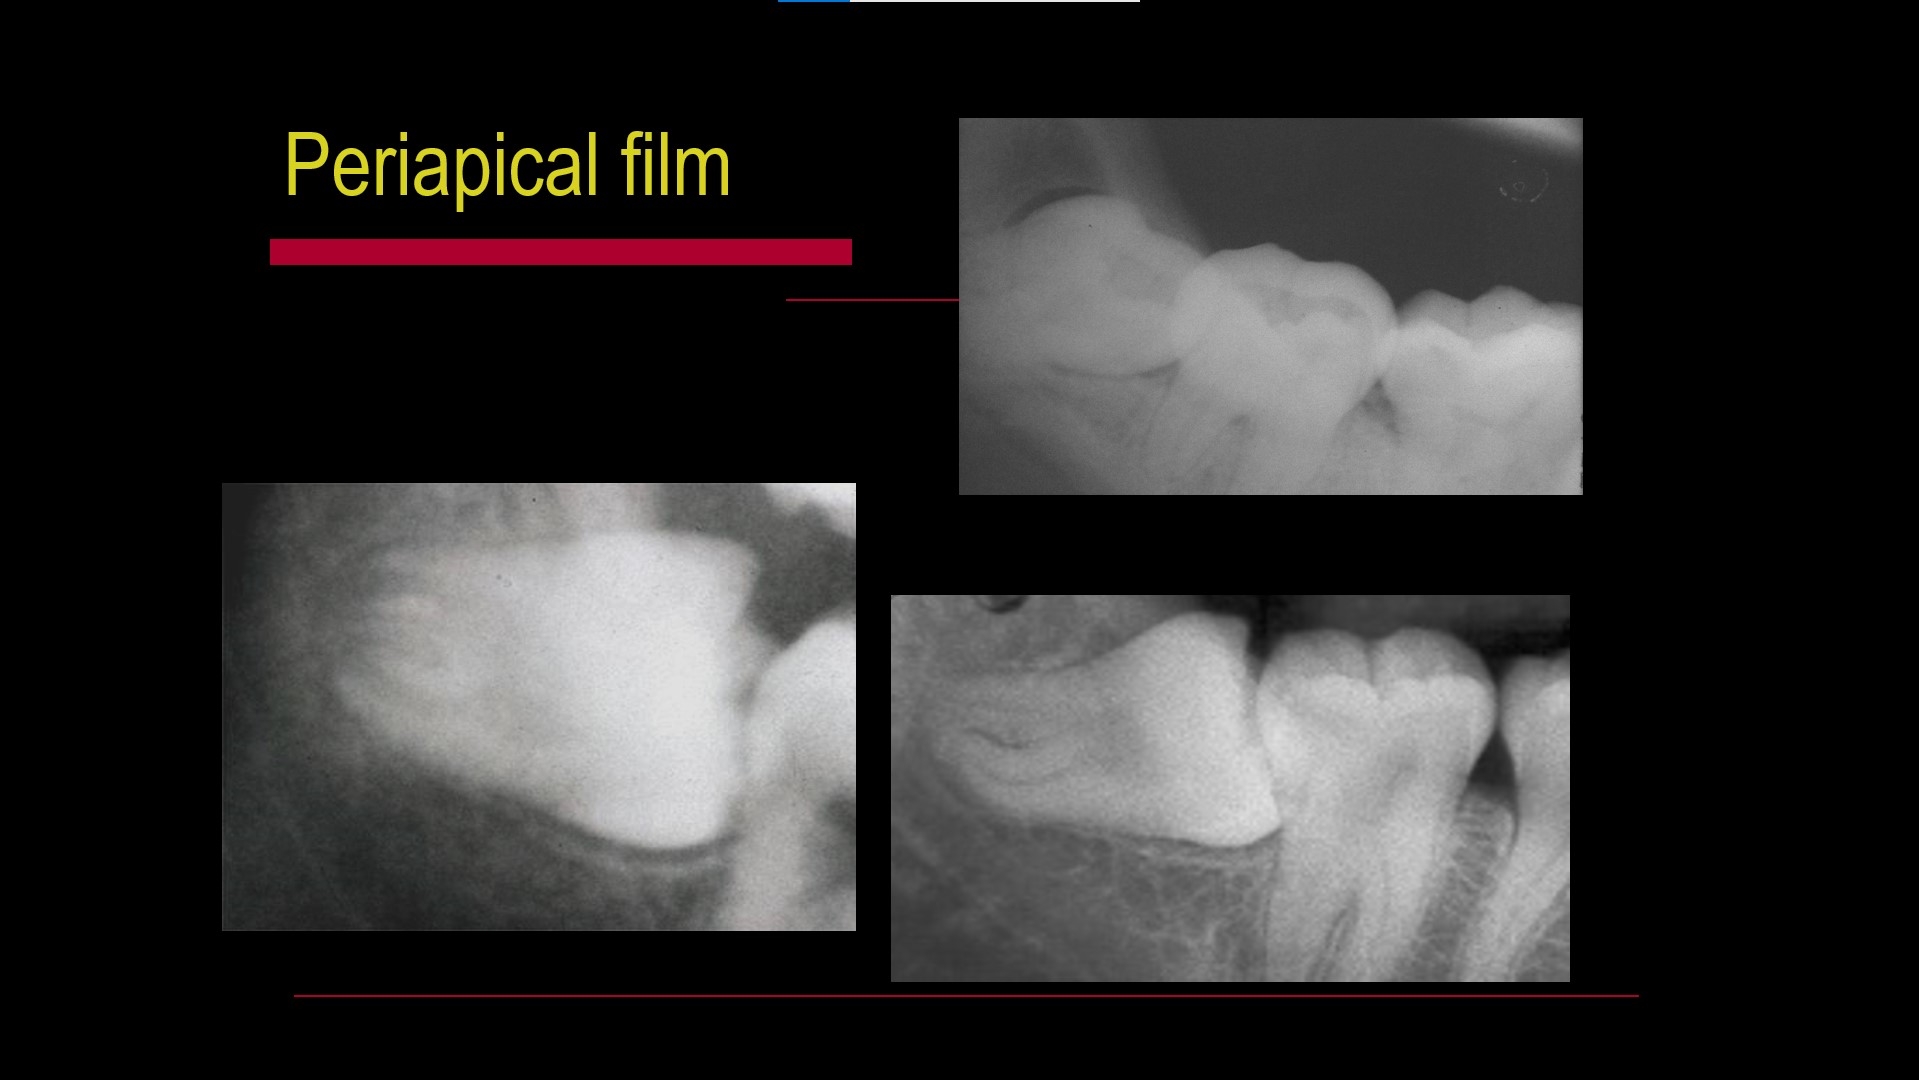

Impacted teeth